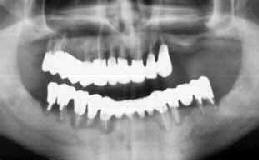

| 上顎でまともな歯は7|35だけ 49歳 男性 |

7|3を残して歯槽骨完全破壊! |

初診時口腔内およびX線所見:

初診は今から17年前(38歳の時)。口腔内清掃状態が悪く、年齢の割に歯槽骨の吸収が

著しかった。当初より歯周疾患の危険性を説明するも、主訴の治療が終わると来院が途絶える

こと2回。3度目の正直で、いよいよ上顎前歯部の動揺が著明になっての再来であった(49歳の時)。

相変わらずの清掃状態と、中程度以上の歯槽骨破壊に愕然とする思いであった。「前から言うてた

歯槽膿漏の手術をして!」と今更言われても…。

処置および経過:

上顎はやや諦め加減で、それでも気を取りなおして全顎のFop+HAP(人工骨移植)を行い、

補綴物による連結固定を施した。治療終了後は、それまでと打って変った様に毎月の

メインテナンスに応じて5年ほどは経過良好のように思われた。しかしそののち、上顎の

あちらこちらに腫脹が見られるようになり、いよいよ今回、7|3を残して上顎残存歯

を抜歯して義歯にすることを決断。

下顎は、「8を除いて経過良好。

考察:

メインテナンスが真面目だった割に、上顎の歯槽骨吸収を阻止することができなかった。その

理由として考えられるのは、以下の通りである。

感想:

メインテナンスが真面目だっただけに、もう少し永く機能して欲しかった!!

| 術前(初診時) パノラマ | 術後(治療終了時) パノラマ |